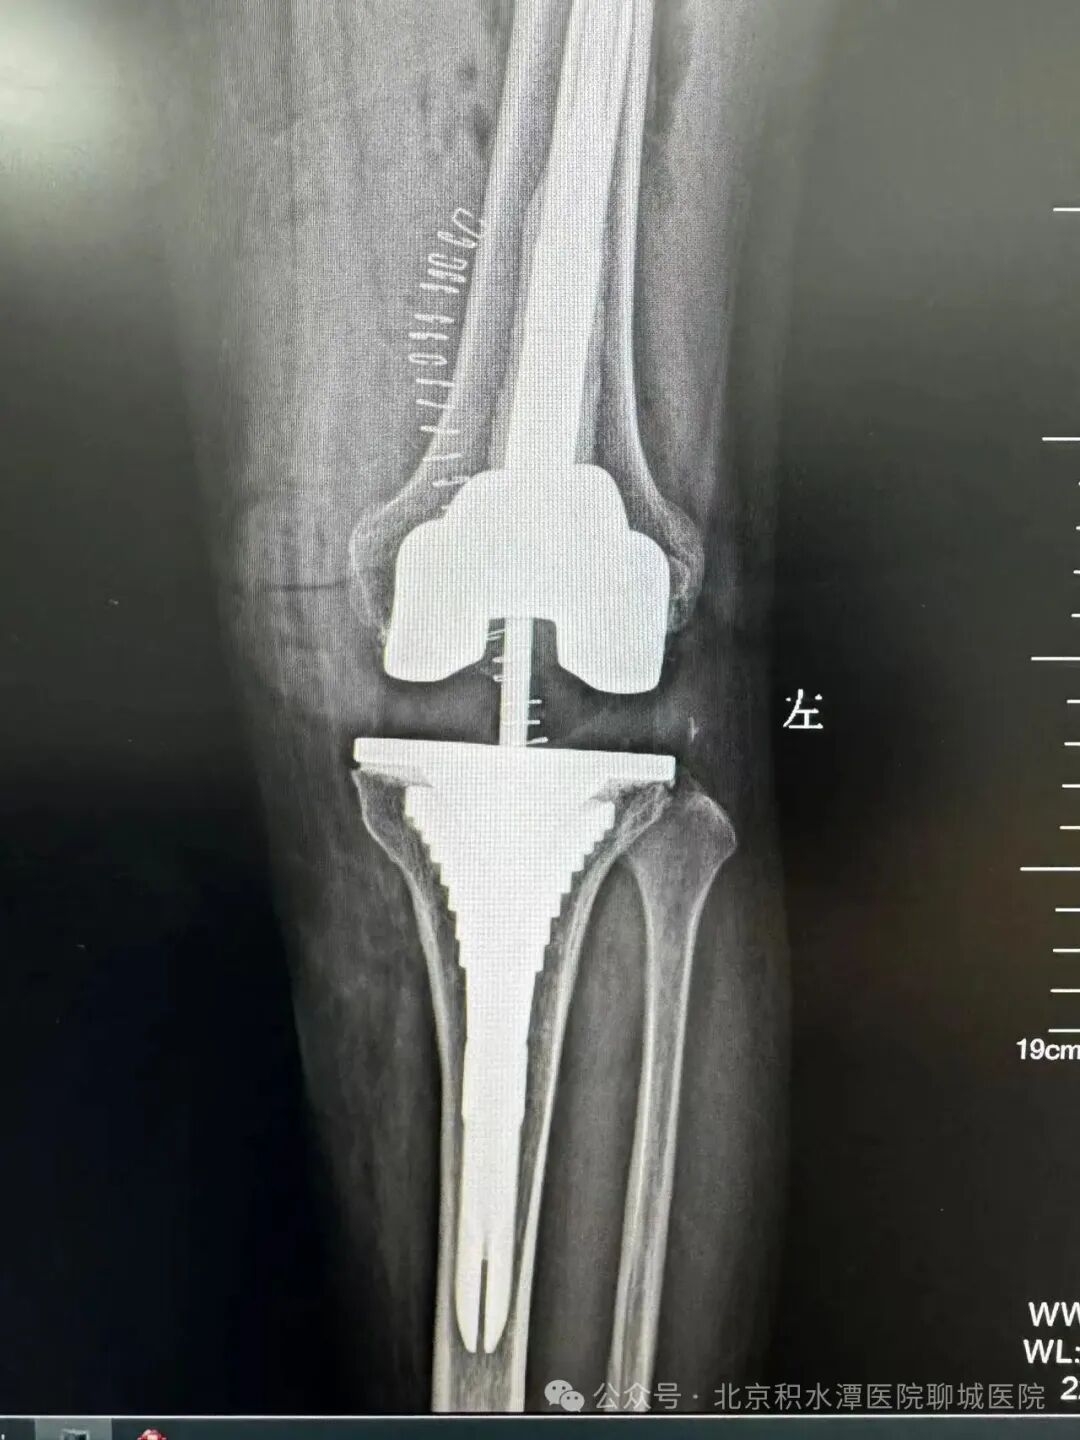

(术前影像)

基于对“隐匿性关节不稳”的清晰认知,徐辉教授团队制定了科学且极具突破性的手术方案,在保留患者自身骨量的同时,精准移除失效部件,并创新性地采用非水泥生物型假体固定技术(聊城首例)。该技术依靠假体表面特殊的生物活性涂层,诱导患者自身骨组织在术后长入假体微孔,实现更持久、更稳固的生物学骨整合,相较于传统骨水泥固定,尤其适用于翻修病例中骨条件相对较好的患者,大大提升了假体的长期稳定性。同时,手术选用了先进的“旋转平台型聚乙烯衬垫”,这一设计允许衬垫在金属底座上发生生理性旋转,显著降低了假体间的剪切应力和聚乙烯磨损,进一步提高了关节的包容性和稳定性,有效降低了远期再松动的风险。